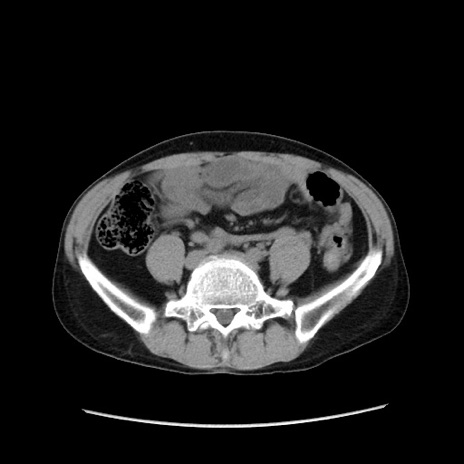

症例37(横断像)

【症例】40歳代 男性

【主訴】腹痛

【現病歴】4時間ほど前に電車に乗車中に臍部上より腹痛出現。徐々に増悪し起立困難となり、救急外来受診。生ものは数日食べていない。今朝お雑煮を食べた。

【身体所見】BT 36.8℃、BP 117/84mmHg、HR 91/min、SpO2 97%、苦悶様、腹部:臍上部広範囲圧痛あり、反跳痛±

【データ】WBC 8100、CRP 0.03